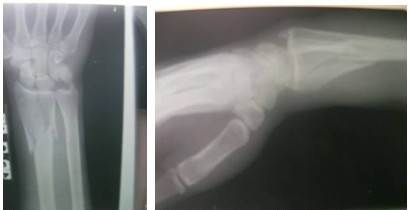

La paciente a su llegada al Hospital fue examinada minuciosamente y sometida a exámenes radiológicos y de laboratorio. (Figuras 1 y 2).